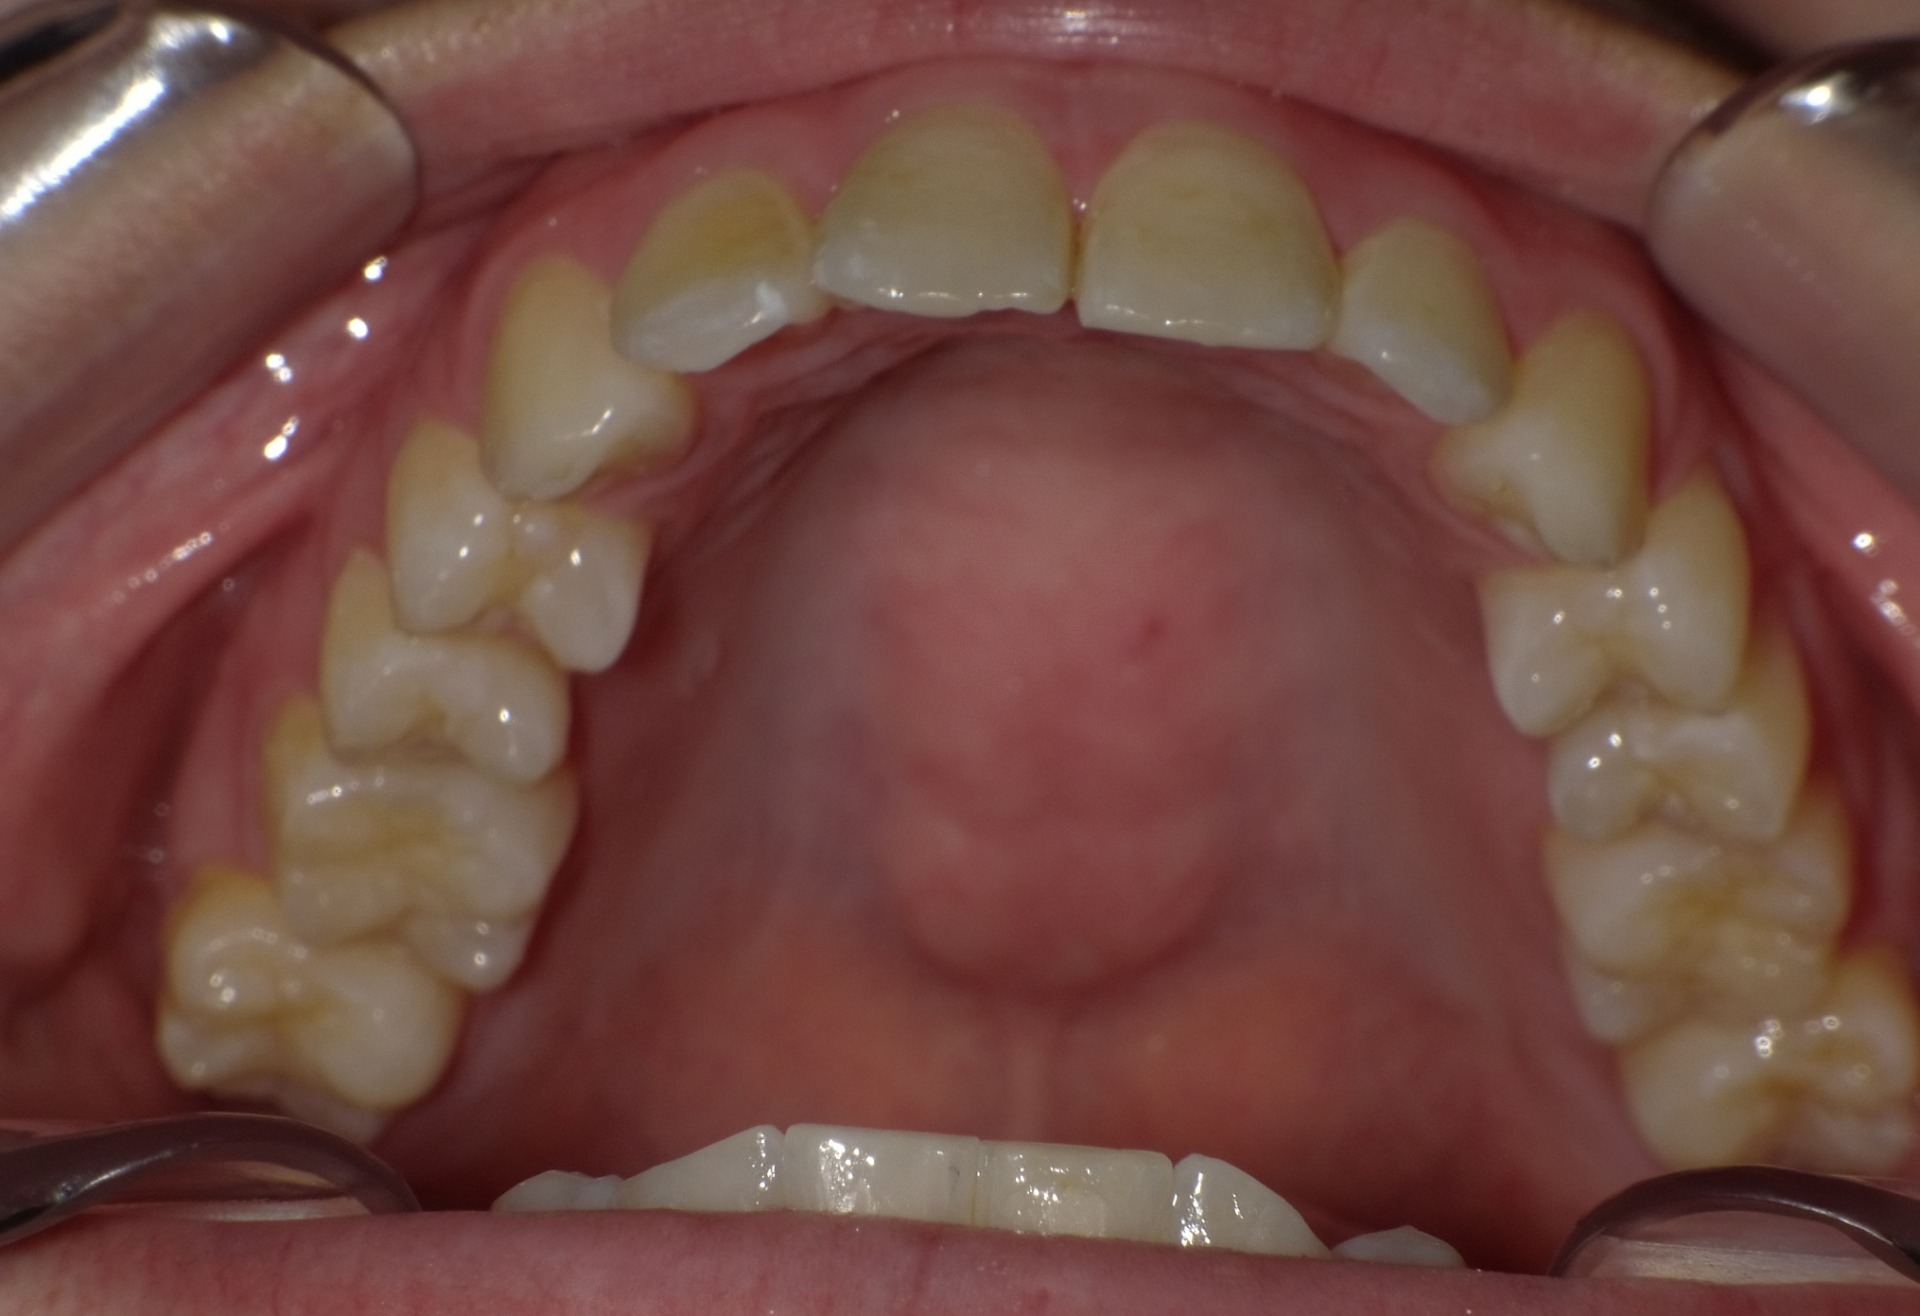

Before